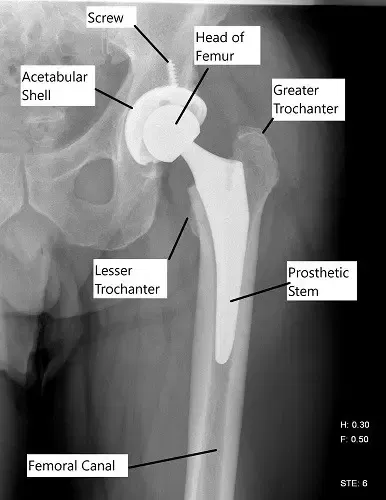

X-ray showing a total hip replacement.